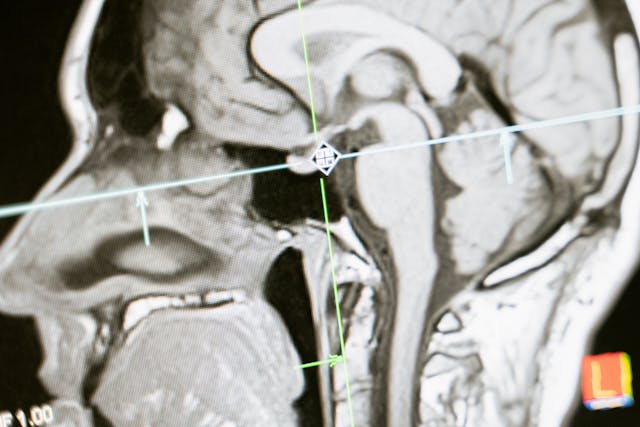

✅ 1. 정기 건강검진 필수! (특히 MRI, CT 촬영) 🏥